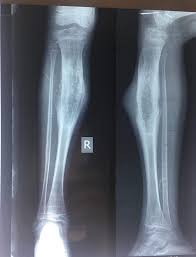

Adolescent X Ray Leg Ap Lateral Views Showing Large Expansile Sclerotic Lesion Noted In The Diaphysis Ewing S Sarcoma Human Anatomy And Physiology Radiology